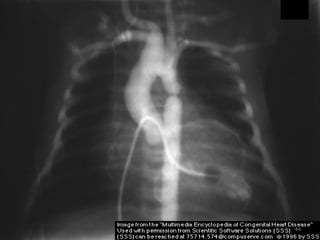

CXR - Narrow base & uplifted apex

- A boot or wooden shoe

- decreased pulm. vascularity

- Right side aortic arch in 20%